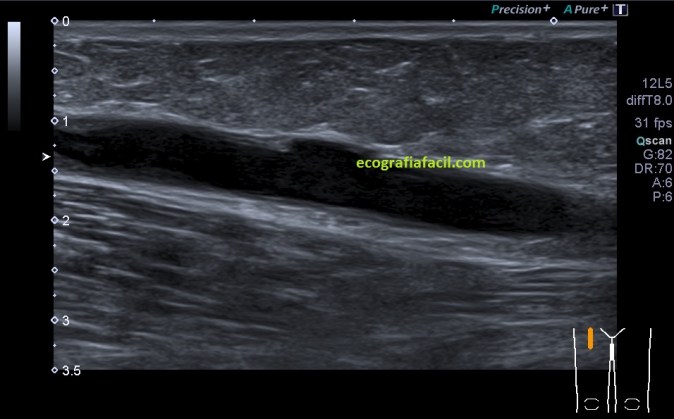

Desde la ingle derecha barrí inferiormente con el transductor, mi sorpresa, a muy pocos centímetros una imagen anecoica redondeada que parecía contener algo, imagen 2, lo primero que pensé fue en una adenopatía, pero al girar la sonda vi que la estructura se alargaba, imagen 1, era tubular en longitudinal y circular en transverso, además pude asegurarme de que en su interior había contenido ecogénico a lo largo de ella. Contenido que no era móvil, es decir, estaba adherido a la capa interna del vaso.

La estructura era ecográficamente hiperecogénica, irregular, ocupaba parte de la luz del vaso, en algún tramo, casi en su totalidad.